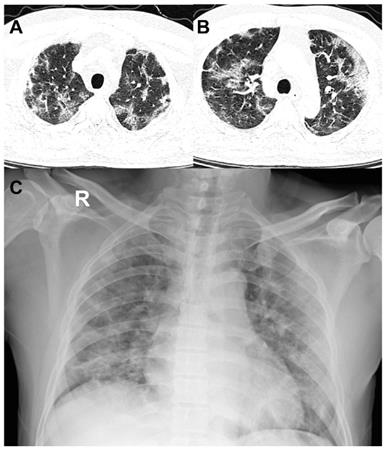

Secondly, in terms of distribution, the upper lung played an important role in risk evaluation for COVID-19 patients. Previous studies reported worse symptoms related to more pulmonary lesions [10,13,15,23]. However, no detailed distribution information was described. Our study of 421 COVID-19 patients suggested an increased pulmonary lesion in bilateral upper lungs were independent risk factors for adverse clinical outcomes, which as far as we know, has not been reported. This finding is of significant clinical implications, not only in providing us a simpler way to identify high risk patients on CT, but also has potential to extend to chest radiographs, where upper lobe consolidations are easy to be perceived. (Figure 6).

Figure 6

52-year-old man with coronavirus disease 2019. A-B. Non-contrast CT was performed on day of admission. C. Chest X-ray was performed on day of admission. Patient developed acute respiratory failure at the second day of hospitalization. Chest CT images showed large areas of bilateral consolidation and ground-glass opacities in upper lungs and lesions showed peripheral distribution. Consist with CT, chest X-ray also showed patchy consolidation in bilateral lung periphery.

Theranostics Image